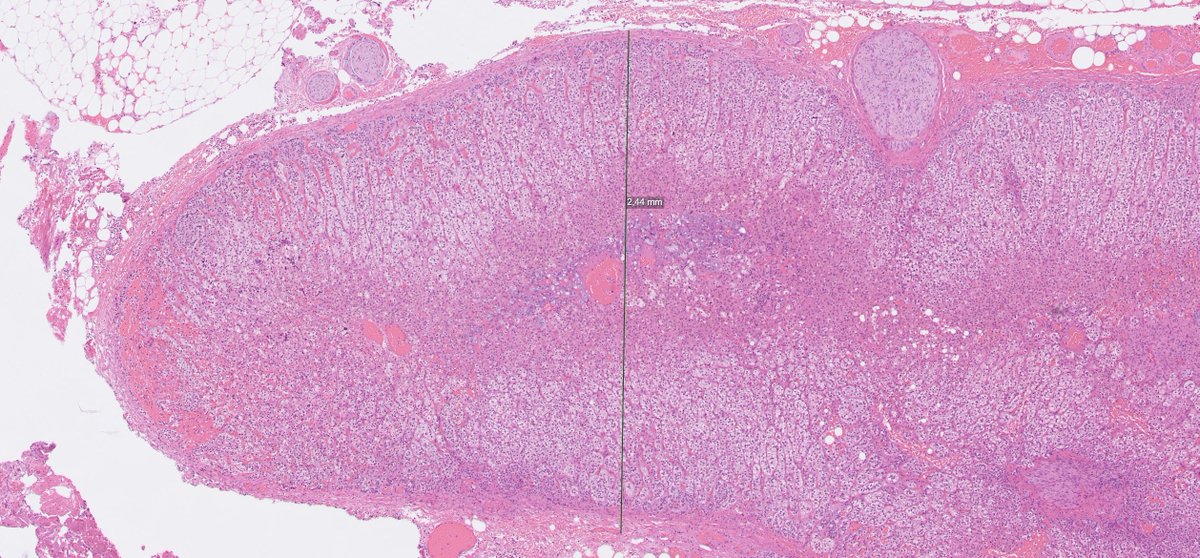

Multiple aldosterone producing nodules are associated with an increased risk of biochemical recurrence in the contralateral adrenal (top row). This specimen also contained an unrelated ganglioneuroma (bottom row) with typical macroscopic/microscopic features. #endopath #GUpath